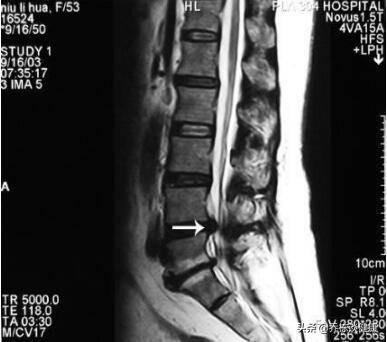

いわゆる腰椎椎間板ヘルニアは、実際には、椎間板の繊維輪の破裂であり、破裂場所から内部の髄核組織が溢れ、対応する脊髄神経根の圧力刺激、このように深刻な背中と脚の痛みを生成し、臨床データから、腰椎突出患者群、L3-4、L5-S1突出病変が最も高い確率を持っています。

腰椎椎間板ヘルニア

腰椎椎間板ヘルニアとは、腰椎椎間板の構成が加齢とともに変化し、蓄積された負担により、椎間板の物理的・化学的性質が変化し、外力が加わると、線維化が破裂し、髄核が突出して神経を圧迫・刺激し、腰痛や下肢痛を引き起こす、一種の病変である。